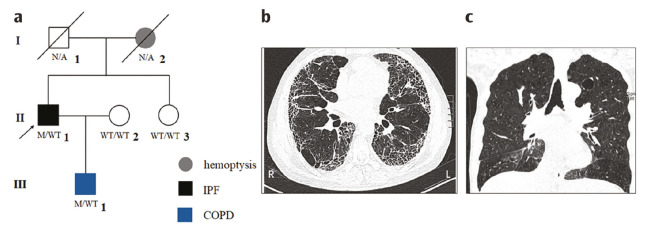

Results: We identified a rare mutation, c.2669G > A (p. Gly890Asp), in TERT (NM_198253.2) in the proband and another affected family member. Bioinformatics analysis predicted this mutation to be deleterious, and structural modeling suggested that it altered the structure and surface charge distribution of the TERT protein. Additionally, real-time PCR demonstrated that mutation carriers had significantly shorter telomere lengths compared with individuals of the same age. According to American College of Medical Genetics and Genomics guidelines, this rare mutation was classified as likely pathogenic.

Conclusions: This is the first reported case of IPF caused by the p. Gly890Asp mutation of TERT in the Chinese population. Our findings support the diagnosis of IPF in the patient and further highlight the role of TERT in the disease.